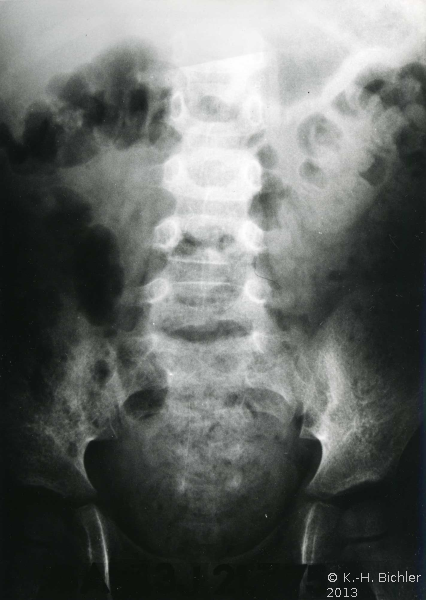

Papillennekrose

Sie tritt zumeist bei Patienten mit Diabetes Mellitus bzw. bei Harnwegsobstruktionen auf (Komplizierte Pyelonephritis). Dabei können eine oder alle Papillen befallen sein. Histologisch findet sich eine koagolative Infarktnekrose, d.h. die Umrisse von befallenen Tubuli sind erhalten. Leukozytäre Reaktionen finden sich an den Rändern der Nekrosebezirke Literatur:Robbins: "Pathologic Basis of Disease", Saunders Philadelphia, 1999.